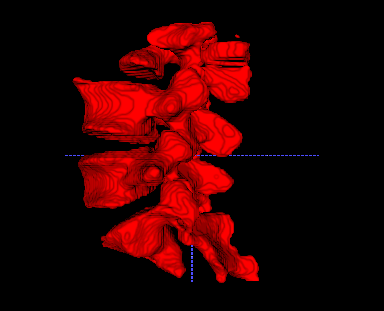

To further improve the segmentation performance, we introduce the 3D segmentation network as in Fig. 3. Our 3D model increases the Dice score from 0.819 to 0.926 and reduces the average ASD by 44% (from 1.47mm to 0.82mm). As shown in Fig. 7, the typical inter-slice discontinuous problem happening in 2D segmentation is fixed with our 3D model, which also runs over 100 times faster than slice-by slice 2D segmentation as measured on a PC with an Intel Xeon E5-2678 and a Nvidia GeForce GTX 2080 Ti.

2D Net

3D Net